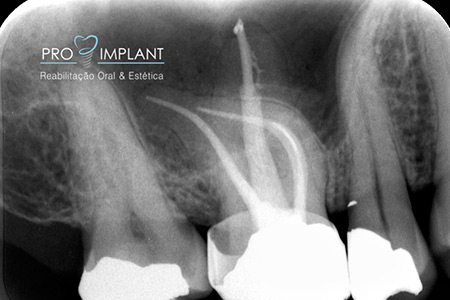

FOTOS

Endodontia